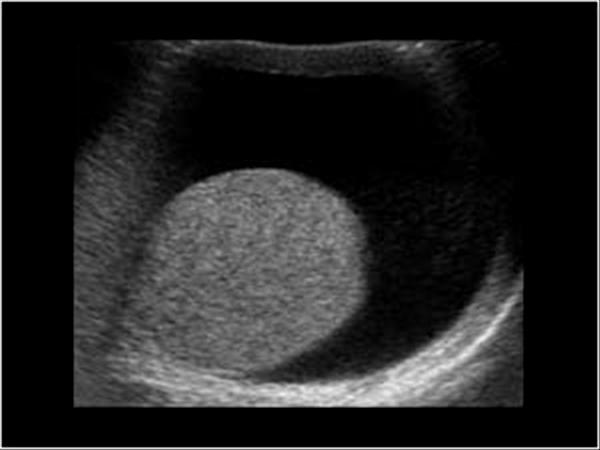

most common germ cell tumor

white male smoker

infertility

Seminoma

25 - 35 year olds